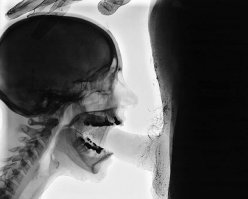

Череп китайского иммигранта Чен Лю, которому 34 раза выстрелили в голову из пневматического гвоздострела